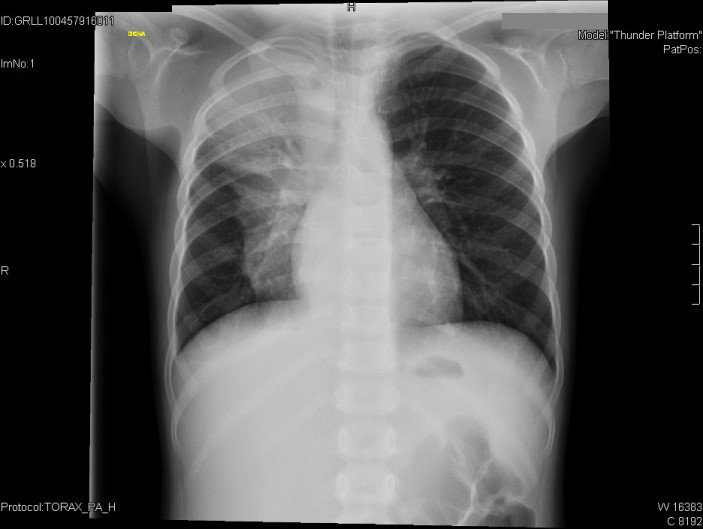

Como hemos constatado, la exploración física manifiesta una discreta disminución de la entrada de aire en el hemitórax derecho.

• Radiografía de tórax: aumento de densidad en lóbulo superior e inferior derecho, con componente atelectásico en lóbulo superior.